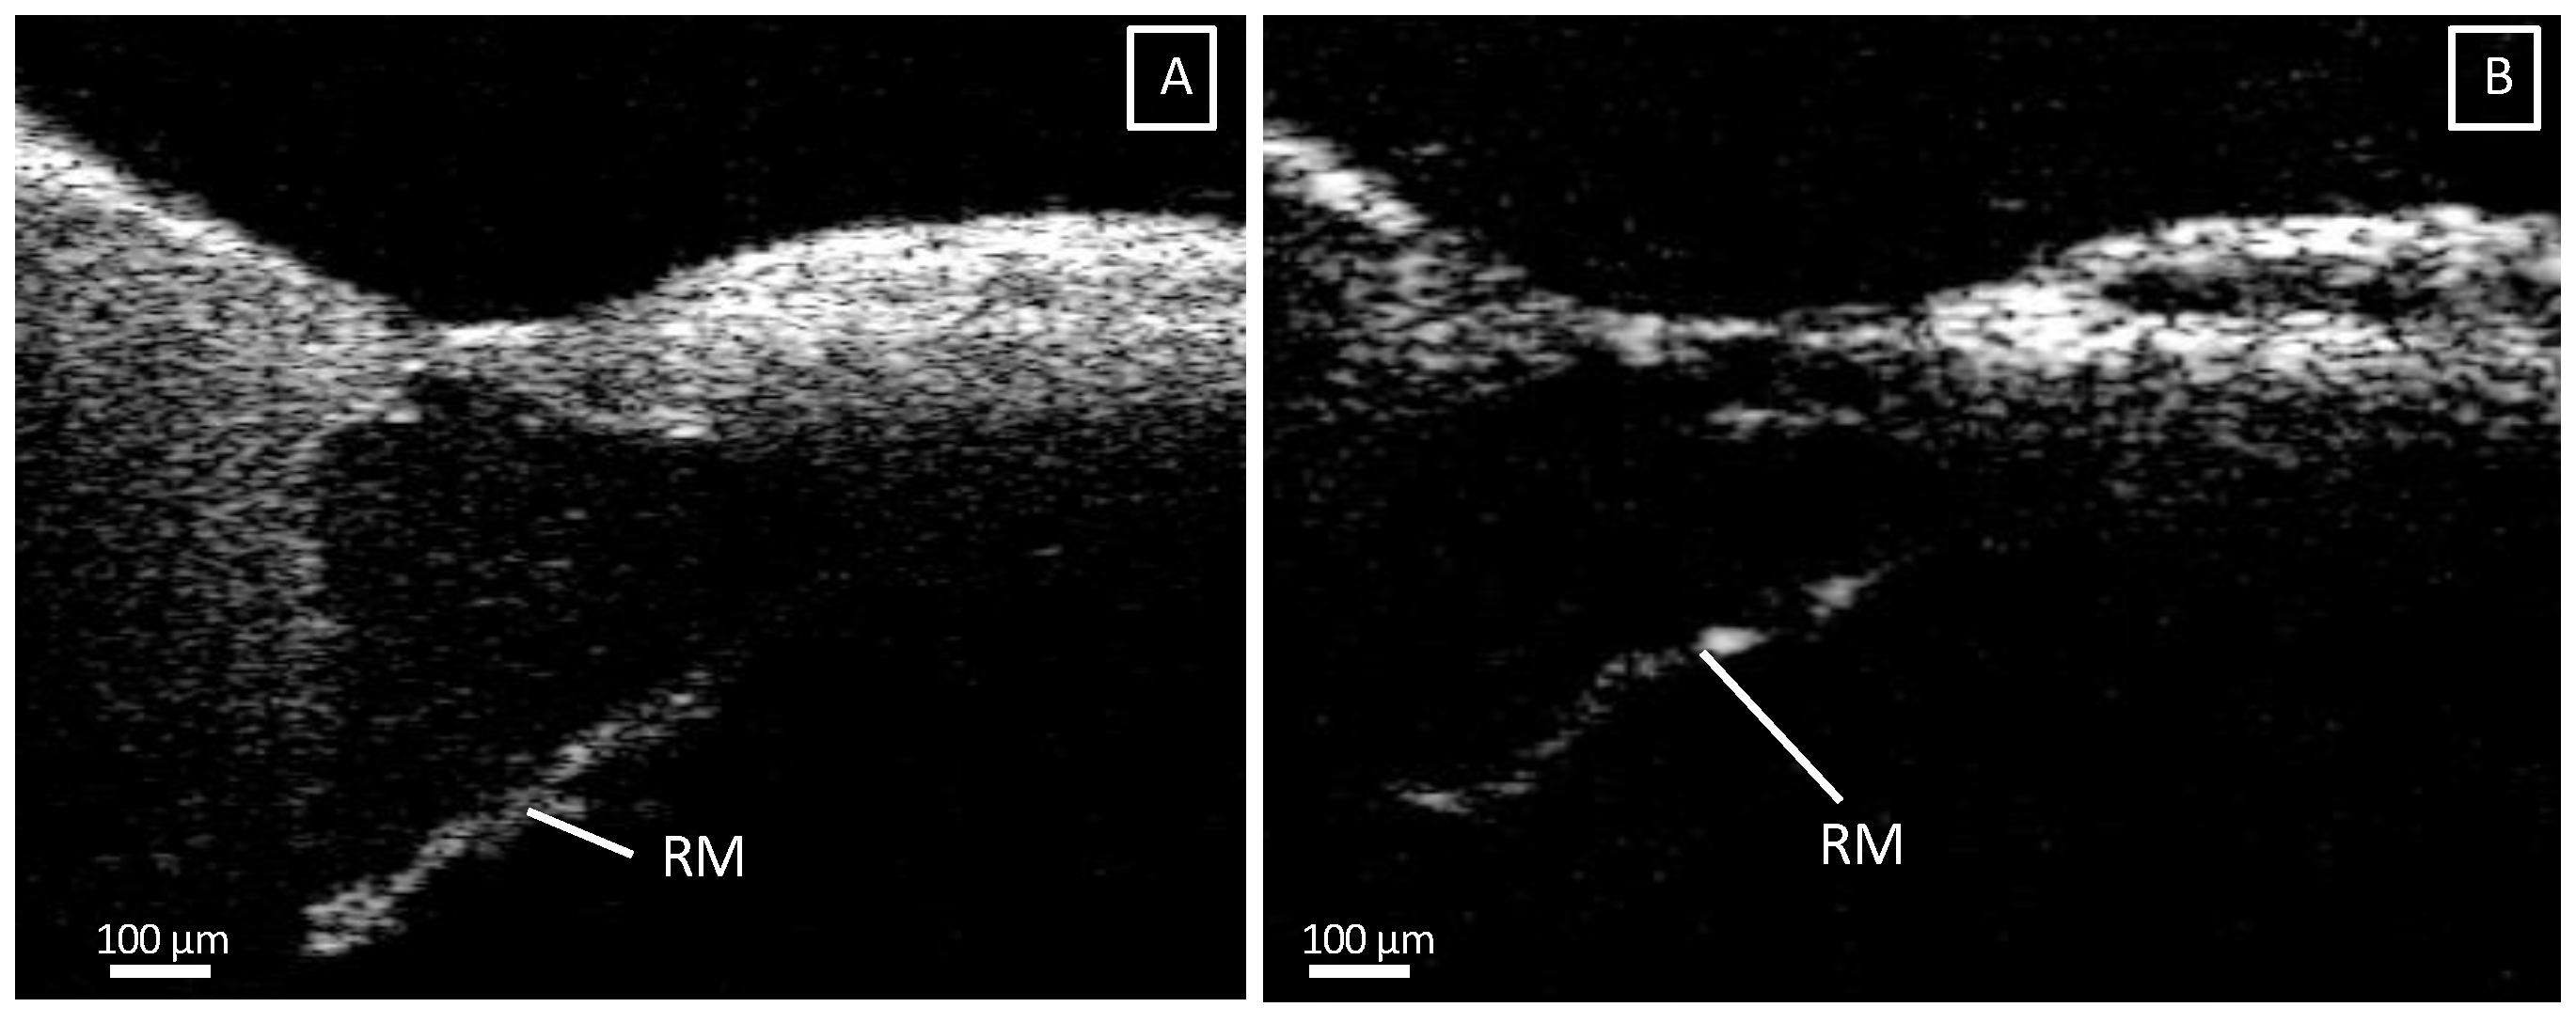

3.1. Intracochlear Microanatomy

3.4. Deviating Appearance of Intracochlear Structures